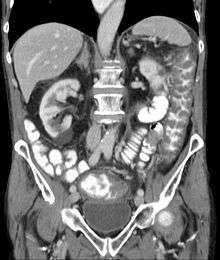

| Pathological specimen showing pseudomembranous colitis | |